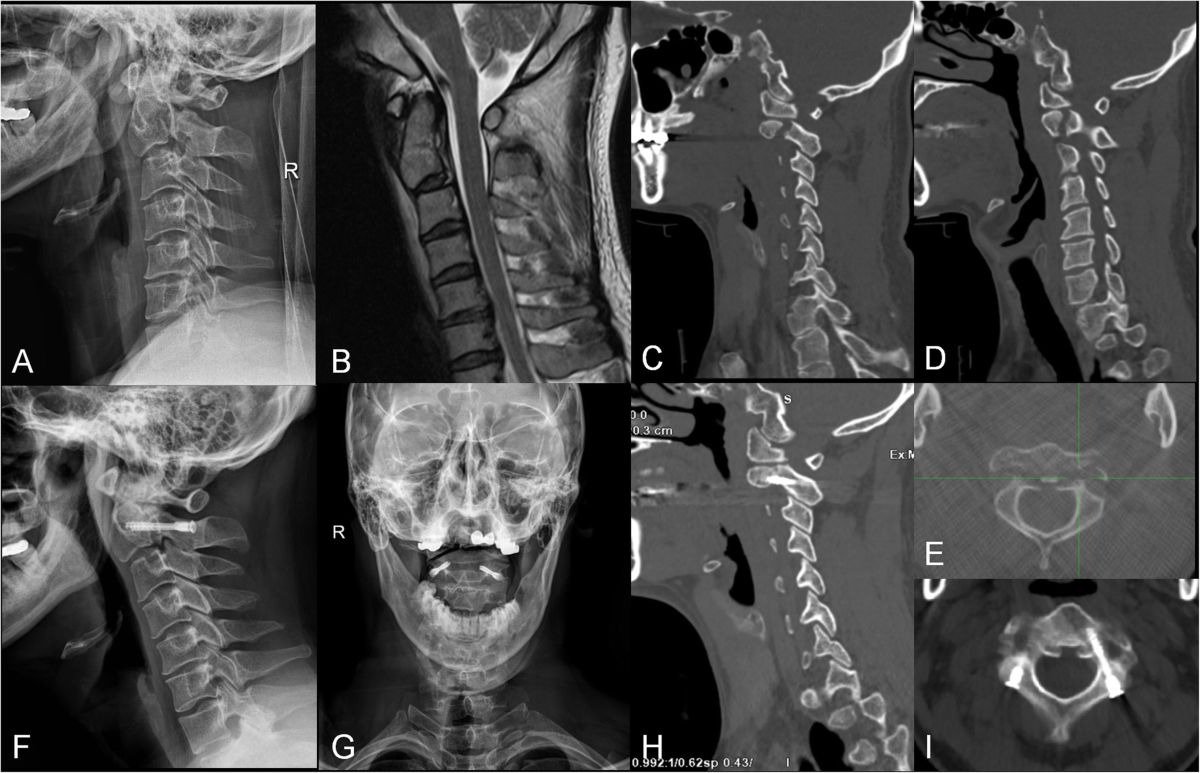

Surgical Management of Hangman's Fracture: A Systematic Review |  International Journal of Spine Surgery, image size:1692x1800

Surgical Management of Hangman's Fracture: A Systematic Review | International Journal of Spine Surgery

Traumatic hangman's fracture after cervical disk arthroplasty with device  in-tact: A case report and literature review - North American Spine Society  Journal (NASSJ), image size:3083x2451

Traumatic hangman's fracture after cervical disk arthroplasty with device in-tact: A case report and literature review - North American Spine Society Journal (NASSJ)